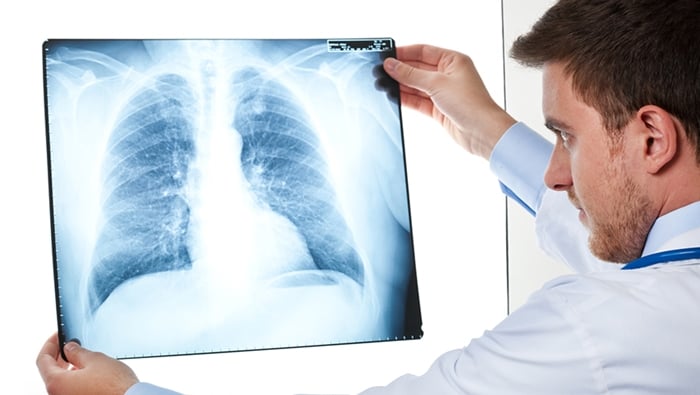

O objetivo de uma clínica de radiologia não é fornecer consultas, de forma alguma. A clínica é feita para realizar serviços de radiodiagnósticos: mamografia, medicina nuclear, radiologia médica e odontológica, densitometria óssea, fluoroscopia. As atividades realizadas são somente para laboratório radiológico e contam com pessoal especializado.